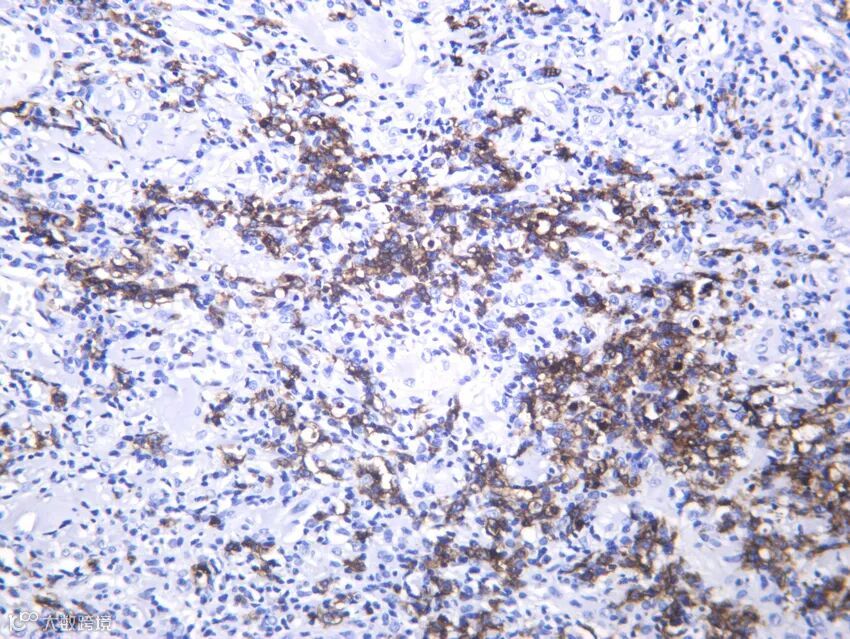

例如,传统的通用神经内分泌标志物包括突触素(synaptophysin)和嗜铬粒蛋白A(chromogranin A),神经内分泌肿瘤(NET)/嗜铬细胞瘤(PHEO)/副神经节瘤(PARA)基本始终表现出弥漫性强嗜铬蛋白A和/或突触素阳性,若染色弱于此则诊断存疑;但是,约1/4的神经内分泌癌(NEC)为嗜铬粒蛋白A/突触素阴性,在NEC中INSM1取代了嗜铬粒蛋白A和突触素成为特异性诊断标记物;Rb失活是小细胞肺癌的分子遗传学标志,是敏感的NEC标记物;≥80%的NEC中可见CXCR4过表达,二者对NEC具有相当的特异性。

肺肿块小细胞神经内分泌癌。(A)肿瘤HE染色,(B)Keratin AE1/AE3呈阳性,(C)突触素和嗜铬粒蛋白A为完全阴性,(D)INSM1呈阳性,(E)Rb表达缺失,(F)CXCR4呈弥漫性强膜染色。